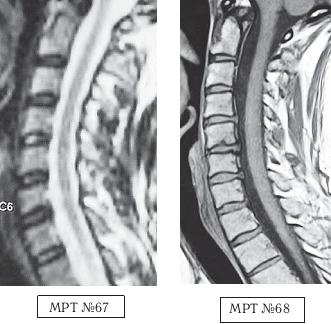

На МРТ № 62 от 07.04.2003 того же пациента наблюдается грыжа межпозвонкового диска LIV-LV с сдавлением дурального мешка, абсолютным стенозом на уровне данного сегмента и увеличением протрузии в сегменте LV—SI. Вот ещё один пример. Произошло это несчастье по причине того, что в течение двух месяцев данной пациентке в одном из специализированных центров врач «вертебролог-вертеброневролог» проводил вытяжения шейного отдела позвоночника с применением петли Глиссона на наклонной плоскости под силой тяжести собственного веса самой пациентки. На жалобы пациентки о том, что после нескольких сеансов самочувствие ухудшилось и усилились боли, врач объяснял, что «это нормально, просто позвонки растягиваются, и межпозвонковые диски становятся на место, поэтому происходит обострение». Но после того как данная пациентка во время очередного сеанса потеряла сознание, ей сделали контрольное МРТ шейного отдела позвоночника (МРТ № 64, была обнаружена секвестрированная грыжа межпозвонкового диска), а затем в срочном порядке направили в нейрохирургию. Этот случай свидетельствует о некомпетентности этого врача «вертебролога-вертеброневролога» и ещё раз подчёркивает, насколько важно в нашем обществе самому пациенту владеть информацией о своём позвоночнике, о процессах, в нём происходящих, и о способах лечения. ![]() На МРТ № 63 наблюдается фрагмент шейного отдела позвоночника. На данном уровне отчётливо видно исправление лордоза, стеноз спинномозгового канала, небольшие протрузии практически компенсированные спондилёзом в сегментах СV-СVI, СVI—СVII, гипертрофия задней продольной связки на данном уровне. На МРТ № 64 наблюдается фрагмент шейного отдела позвоночника той же пациентки через два месяца. На снимке видно, что к имевшимся (на МРТ № 63) проблемам добавилась ещё и грыжа в сегменте СV-СVI, и секвестрированная грыжа межпозвонкового диска в сегменте СVI-СVII.. Следующий пример также довольно типичный, как пациент, из-за недостатка знаний, усугубил состояние своего здоровья. Данный пациент периодически испытывал кратковременные боли в поясничном отделе позвоночника. По его словам, они, как правило, возникали «после длительного сидения, в момент вставания» (стартовые боли) и быстро проходили. Пациент обратился в районную больницу по этому поводу. Сделали МРТ (№ 65). Врачи не обнаружили на снимке существенных патологий, поэтому выписали пациенту лекарства и посоветовали меньше сидеть и больше двигаться. Однако, так как эти боли продолжали доставлять пациенту некоторые неудобства, он решил самостоятельно от них избавиться, причём как обещают в рекламе «раз и навсегда». Для этого он, по его словам, «выбрал для себя наиболее удобный способ». То есть, приобрёл широко рекламируемое устройство для вытяжения позвоночника в домашних условиях. На протяжении нескольких месяцев он добросовестно выполнял предписания из инструкции, прилагавшейся к этому устройству. Как это обычно бывает, вначале действительно стало немного легче, но этот эффект длился недолго. Внезапно появились тянущие боли в ноге. Пациент вновь вынужден был обратиться за помощью в больницу, но дома всё равно продолжал вытяжения позвоночника. А после того как боли усилились настолько, что лекарства уже не помогали, ему повторно сделали МРТ (МРТ № 66). Естественно, ознакомившись с результатом обследования, врачи направили его в нейрохирургию. Вот к каким последствиям приводит отсутствие элементарных знаний и слепая вера во «всесильную» рекламу. Если бы данный пациент знал заранее, к чему может привести вытяжение позвоночника при дегенеративно-дистрофических процессах в позвоночнике, то уж точно не стал бы так рисковать своим здоровьем. ![]() На МРТ № 65 наблюдается нормальный физиологический лордоз, снижение высоты межпозвонкового диска в сегменте LV—SI, вследствие развития в нём дегенеративно-дистрофического процесса (остеохондроза). На МРТ № 66 наблюдается сглаженность физиологического лордоза, грыжа межпозвонкового диска в сегменте LV—SI. Ещё один показательный пример о том, как молодая девятнадцатилетняя девушка попала к «чудо-новатору» по методам вытяжения позвоночника. Началась данная история с того, что у молодой студентки, вследствие длительной работы на компьютере, стали появляться боли в мышцах шеи и плеч. Она обратилась к врачу. Этот «специалист» после осмотра поставил ей предварительный диагноз — «смещение диска» и направил на МРТ. Заметьте, на первый взгляд врач действовал правильно, направив пациента на МРТ уточнить диагноз. Но как потом оказалось, для него это являлось всего лишь формальностью, а не установлением истинной причины происхождения болей и тем более не заботой о выборе щадящих методов лечения. Впрочем, судите сами. После результатов обследования, в описании которого была указана только протрузия в сегменте CVI-CVII размером 1,4 мм центральной локализации, данный врач объяснил, что «это и есть смещение диска, который давит ей на нерв» и предложил его вправить, на что девушка, по своей наивности и из-за отсутствия элементарных знаний о развитии патологии в позвоночнике, согласилась. Более того, на её беду (в прямом смысле слова) этот врач оказался новатором-изобретателем. По его словам, он «совершил настоящую революцию в вертебрологии» (сам он травматолог), «изобрёл чудо-устройство, с помощью которого можно навсегда избавить пациента от остеохондроза». Я не утрирую, это действительно слова данного «специалиста». Он стал рассказывать девушке, что «изобретение» настолько эффективное, что к нему даже японцы приезжали с просьбой продать им это «чудо», но не продал (не по причине патриотизма), просто потому, что японцы хотели его обмануть и предложили слишком мало денег, «всего два миллиона евро». В данном случае вы сами понимаете, что ни о какой порядочности и врачебной этике такого «специалиста» говорить не приходится, если в голове вместо знаний науки вертебрологии только подсчёт количества нулей. ![]() На МРТ № 67 от 17.09.2009 наблюдается шейный отдел позвоночника с признаками формирования протрузий в сегментах CV—CVI, CVI—CVII. Физиологический лордоз сохранён, признаков нарушения проводимости ликворных путей не наблюдается. На МРТ № 68 от 12.10.2009 у той же пациентки наблюдается значительное прогрессирование дегенеративно-дистрофического процесса в шейном отделе позвоночника с осложнениями в виде грыж межпозвонковых дисков CIV-CV, CV-CVI, CV—CVII, сглаживание физиологического лордоза с нарушением ликвородинамики. В действительности же этим «чудом» оказался всего лишь раздвижной стол с изменяемым углом наклона для растяжения позвоночника. Со слов пациентки, её «положили на этот раздвижной стол, к нижней половине стола привязали ноги и таз в районе талии, а к верхней половине привязали голову под челюсть и затылок (очевидно петлёй Глиссона) и начали крутить какую-то ручку, стол стал раздвигаться и наклоняться вниз». После того как вследствие растяжения шейного отдела позвоночника у данной пациентки появились сильные боли, врач сказал «терпеть» и оставил её в такой «растяжке» на десять минут. После чего пояснил, что таких сеансов «вправления выпавшего диска» ей надо пройти как минимум десять и тогда всё будет хорошо. До десяти сеансов пациентка не дотянула, так как «хорошо» ей уже стало после шестого сеанса, начались синкопические состояния (состояние перед обмороком), боль и онемение в правой руке, головокружение и нарушение координации при ходьбе. |